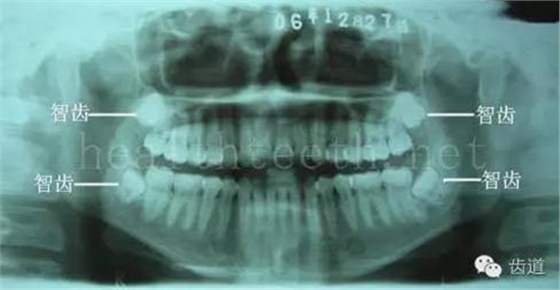

因?yàn)楸旧聿桓阏衬げ。占降牟±邢?,大多是同事收?/span> 頰粘膜扁平苔蘚 舌粘膜扁平苔蘚 舌緣創(chuàng)傷性潰瘍 長期戴活動義齒不當(dāng)或是戴不良修復(fù)義齒造成的口腔粘膜潰瘍,應(yīng)該引起高度警惕,因?yàn)檫@種潰瘍?nèi)菀装┳?/span> 黑毛舌 舌息肉,該患者同時伴有胃、食管息肉,后來看內(nèi)科了,具體情況不詳 四、孩子的牙齒問題 乳牙未退,牙根穿出牙齦對上唇粘膜造成刺激 乳牙滯留,也是孩子在退牙過程中最容易遇到的問題 五、牙齒發(fā)育上的問題 變色牙 氟斑牙 釉質(zhì)發(fā)育不全 四環(huán)素牙 牙神經(jīng)治療后的牙齒變色 10歲孩子剛剛萌出的牙齒變色 2、埋伏牙 左上乳3滯留,恒3未見萌出,曲面斷層片顯示牙齒埋伏 通過CT片確定埋伏牙齒具體的位置,顯示距離左側(cè)上頜竇很近,偏唇側(cè),這為手術(shù)定位提供了方便 手術(shù)中切斷、完整拔出,未損傷上頜竇 其他埋伏牙 3、多生牙 病例1 病例2 病例3,同時多生兩顆牙齒 4、各種畸形牙 畸形過小牙 融合牙:恒牙和乳牙都可以發(fā)生融合的情況(兩顆牙齒長在了一起) 畸形中央尖:在牙齒的中央,兩個牙尖之間又多長出一個牙尖,由于進(jìn)食的磨耗很容易造成磨穿,神經(jīng)就會與外界相通,出現(xiàn)牙髓炎的癥狀 六、牙齒的外傷 牙冠折斷 牙根折斷 烤瓷牙打樁修復(fù)后牙根折斷 外傷后牙齒的全脫位,應(yīng)該保留牙齒盡早做再植手術(shù) 七、牙齒的慢性損傷 牙頸部楔狀缺損 牙冠劈裂及完整拔除后的情況 牙根縱裂及拔除后的情況 牙隱裂,牙齒表面有肉眼看不到的裂紋,細(xì)菌通過其進(jìn)入牙髓,容易出現(xiàn)牙髓炎癥狀,嚴(yán)重可以造成牙齒的劈裂 這是一位來中國學(xué)習(xí)的俄羅斯大學(xué)生的牙齒,已經(jīng)做過了根管治療,牙齒咬合面有隱裂,通過鋼絲結(jié)扎固定,做鑄造金屬冠修復(fù)。 八、牙髓炎、根尖周炎 下面圖片都是慢性根尖周炎的病例,有了齲齒,進(jìn)一步發(fā)展就是牙髓炎,如果此時沒有得到及時的治療,疾病會逐漸發(fā)展破壞到根尖的骨質(zhì),將骨質(zhì)破壞后就在牙齦上出現(xiàn)一個膿瘺,此時患者不再感覺到牙齒的疼痛了,往往忽視了治療,但是這種不痛并不是疾病好轉(zhuǎn)了,而是因?yàn)榧膊〉难仔詽B出得到了引流,這個膿瘺會出現(xiàn)有時候變大了,有時候又變小了,但是如果不治療是不會自己愈合的,只有經(jīng)過完善的根管治療后才有好轉(zhuǎn)的可能,但是在疾病的治療中時間是起決定作用的,時間拖得越晚,好轉(zhuǎn)的可能性越小,經(jīng)過根管治療后如果膿瘺還是沒有消失,就需要做根尖刮治術(shù),如果仍然沒有好轉(zhuǎn),就只能做根尖切除術(shù)了,這對牙齒的穩(wěn)固是不利的。下面圖片中在膿瘺中插入了一個牙膠尖,是我們做根管充填用的材料,是非常軟的,就是在口腔牙齦瘺管的地方插進(jìn)去,通過拍牙片可以清晰地看到它到達(dá)的位置,從而確定發(fā)病的牙齒,此處是為了讓大家看得更清楚。 門牙兩個膿瘺 烤瓷牙修復(fù)后牙齦出現(xiàn)兩個膿瘺,插入牙膠尖,牙片顯示牙膠尖到達(dá)的位置就是根尖炎癥的位置,根尖骨質(zhì)密度降低(發(fā)黑的地方) 牙齒根尖膿瘺,治療前、中、后的圖片對照,完善根管治療后膿瘺明顯消失了 牙髓炎和根尖炎治療的關(guān)鍵就是根管治療 合格的根管充填治療 不良的根管充填治療 九、關(guān)于智齒(第八顆牙) 四顆長不出來的智齒 智齒反復(fù)發(fā)炎造成的頰瘺,膿腫切開引流后面部會留疤 智齒造成的頜骨囊腫,手術(shù)切除后需要植骨 十、各種錯合畸形 開合 深覆合 深覆蓋,上頜前突 反合(地包天) 牙齒排列擁擠 來源:牙醫(yī)愛看的 KQ88口腔醫(yī)學(xué)網(wǎng)